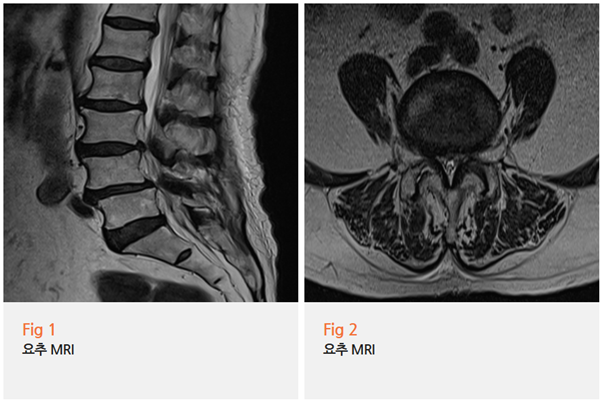

1단계: 요추 MRI

먼저 허리뼈 상태를 확인했습니다.

결과는... 예상했던 대로였습니다.

요추 3-4번, 4-5번 부위에 심한 전방전위증이 보였고,

이로 인한 중증 요추관 협착증까지 확인됐습니다.

쉽게 말하면, 허리뼈가 앞으로 밀려나와서 신경이 꽉 눌려있는 상태였던 거죠.

이 정도면 당연히 다리가 저리고 아플 수밖에 없습니다.